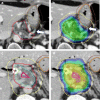

Standard doses of conventionally fractionated radiation have had minimal to no impact on the survival duration of patients with locally advanced unresectable pancreatic cancer (LAPC). The use of low-dose stereotactic body radiation (SBRT) in 3- to 5-fractionshas thus far produced a modest improvement in median survival with minimal toxicity and shorter duration of treatment, but failed to produce a meaningful difference at 2 years and beyond. A much higher biologically effective dose (BED) is likely needed to achieve tumor ablation The challenge is the delivery of ablative doses near the very sensitive gastrointestinal tract. Advanced organ motion management, image guidance, and adaptive planning techniques enable delivery of ablative doses of radiation (> = 100Gy BED) when more protracted hypofractionated regimens or advanced image guidance and adaptive planning are used. This approach has resulted in encouraging improvements in survival in several studies. This review will summarize the evolution of the radiation technique over time from conventional to ablative and describe the practical aspects of delivering ablative doses near the GI tract using cone beam CT image (CBCT) guidance and online adaptive MRI guidance.